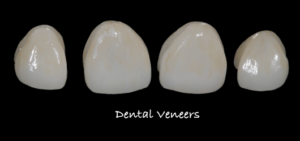

Want a dazzling smile that looks natural? Emax veneers are crafted from translucent ceramic, mimicking the light-reflecting properties of natural teeth for a seamless blend.

A thorough clinical and radiographic examination followed, and we determined that dental veneers would be the most suitable option to address her concerns. We presented her with both composite and ceramic veneer options, explaining the details of each material. Since she had always desired ceramic veneers, that’s what she opted for. To achieve the desired aesthetic outcome, we further determined that E-Max ceramic veneers would be ideal. Here are the steps involved in the treatment plan: